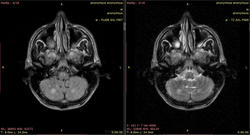

Видны изменения в стволе мозга (мост), белом веществе мозжечка и, помимо этого, белом веществе большого мозга (виден по крайней мере один перивентрикулярный очаг в левой теменной доле, нельзя исключить более мелких очагов - трудно судить по низкопольным картинкам).

Такая картина характерна для центрального понтинного миелинолиза. Он возникает в основном у алкоголиков на фоне острый осмотических нарушений. При этом поражается в основном мост, но также могут быть видны очаги в других отделах мозга (экстрапонтинный миелинолиз). Поэтому и понтинные, и экстрапонтинные изменения объединяются термином "синдром осмотической демиелинизации". Вот здесь разные случаи: http://radiopaedia.org/articles/central-pontine-myelinolysis

C учетом наличия очагов в мозжечке и перивентрикулярно - скорее РС.

Наверное, вы правы. В продолговатом мозге тоже очаги.